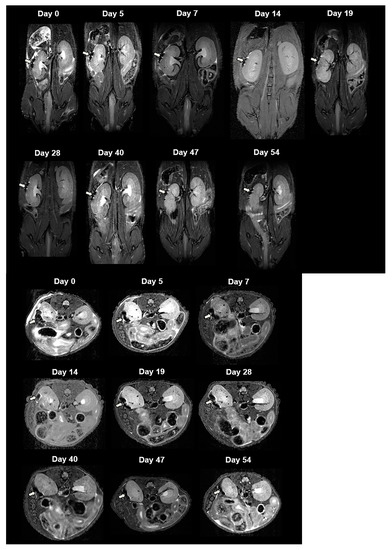

For in vivo MRI, we transplanted 2000 CSPIO-labeled NPCCs under the left kidney capsule of each nude mouse. Three recipients were scanned by a 7.0 T MRI system for up to 54 days. As shown in Figure 3, the graft of CSPIO-labeled NPCCs (indicated by arrows) was visualized as a distinct hypointense area on MR images located at the implantation site between day 0 and 54. This is expected, as we previously visualized CSPIO-labeled islets under mouse kidney capsules on MR scans as persistent hypointense areas after syngeneic and allogeneic transplantation [40,41,42]. The quantification analysis revealed that the MR signal intensity of the graft on the left kidney was significantly reduced compared to the mirror area on the right kidney at all time points (p = 0.000) (Figure 4). Previously, we observed that the MR signal loss was 20% lower in 200 CSPIO-labeled islet isografts than that of unlabeled islet isografts, and this difference persisted for 6 weeks [40]. In this study, 2000 CSPIO-labeled NPCC grafts made a persistent 60–80% reduction of MR signal for 54 days as compared to the same area in the contralateral kidney. To the best of our knowledge, we are the first to use MRI for the detection and monitoring of NPCC grafts.

Figure 3.

In vivo MR image of NPCCs after transplantation. Two thousand CSPIO-labeled NPCCs were transplanted under the left kidney capsule of a nude mouse. The recipient was scanned by a 7.0 T MRI system with coronal (upper panel) and transverse (lower panel) sections. The graft of CSPIO-labeled NPCCs was indicated by arrows.